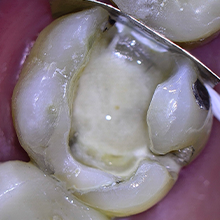

Vedamento Marginal, selando a fratura com Cimento Super-Bond

Trabalhamos também com materiais da Sun Medical, empresa japonesa reconhecida mundialmente pela excelência em sistemas adesivos. Entre eles está o Super-Bond C&B, um cimento resinoso químico utilizado há mais de 40 anos no Japão e amplamente estudado na literatura científica.

Em nossa prática clínica, utilizamos o Super-Bond principalmente em situações que exigem adesão extremamente confiável, como cimentação de pinos, coroas e manejo de dentes com trincas, contribuindo para aumentar a previsibilidade e a longevidade dos tratamentos.

O Super-Bond não é apenas um cimento resinoso; é um divisor de águas na odontologia adesiva que, após quatro décadas de sucesso clínico no Japão, finalmente chegou ao Brasil. Com uma tecnologia baseada no monômero 4-META e no iniciador TBB, ele oferece uma polimerização química impecável mesmo em condições de umidade, penetrando profundamente em microespaços onde outros sistemas falham.